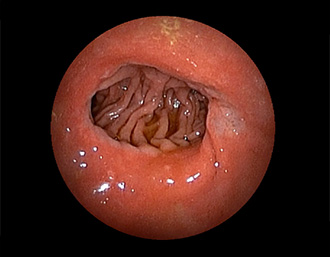

症例5:胃腺腫(84才女性)

胃角部に、大きさ10mm強のなだらかな粘膜隆起を認める。生検:Tubularadenoma with moderate atypia.Group 3。経過観察中。

通常画像